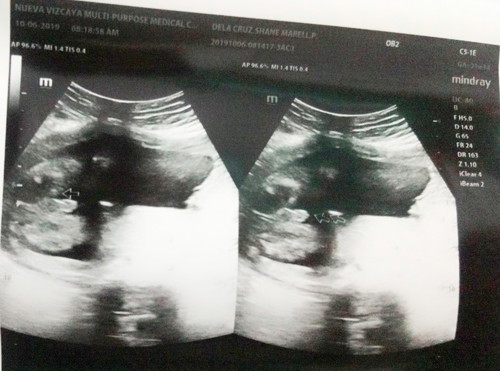

Guess kng ano? S mga dp mrunong tumingin ng gender, try nyo po if mahulaan nyo po

Ilang weeks po tummy nyo nung ng pa ultrasound kayo.. Its baby boy eh.. 😍

Baby boy. May lawit haha, congratulations po! 😍

Baby boy kita unq itloq eh hahaha

Baby boy. Kitang kita. 😊❤

Yung nakabukaka mo dalawang paa nya yunm yung nasa gitna. Yun yung itlog nya po at toytoy